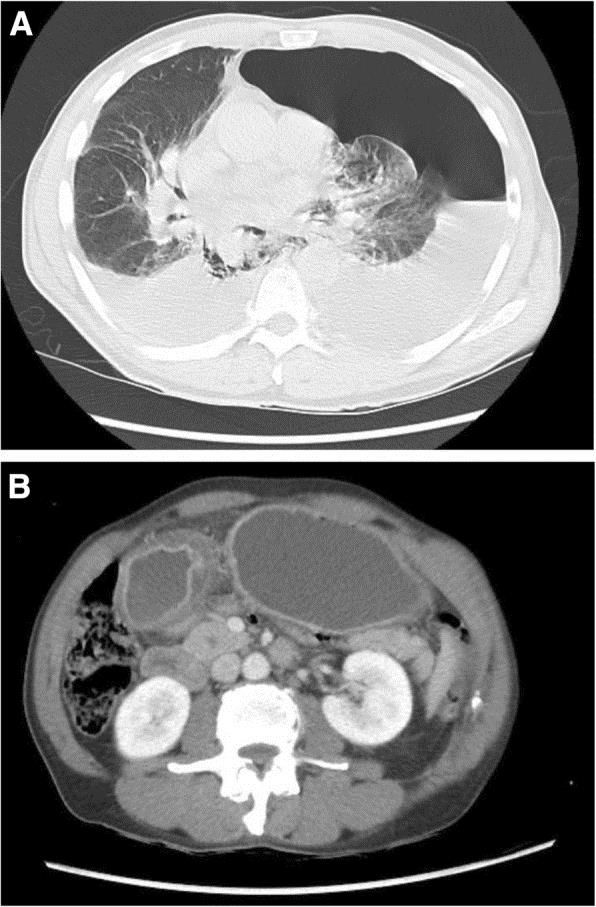

В течение месяца до обращения у него были эпизоды тошноты, рвоты и дисфагии, за последний год он потерял 40 кг. При осмотре зафиксирована тахикардия (110 ударов в минуту), гипотония (86/68 мм рт. ст.) и тахипноэ (до 40 вдохов в минуту), а также болезненность в левой половине грудной клетки. РКТ органов грудной клетки выявила перфорацию пищевода, левосторонний гидропневмоторакс (рис. 1 — A) и утолщение пилорического отдела желудка (рис. 1 — B).

Рисунок 1 [2].